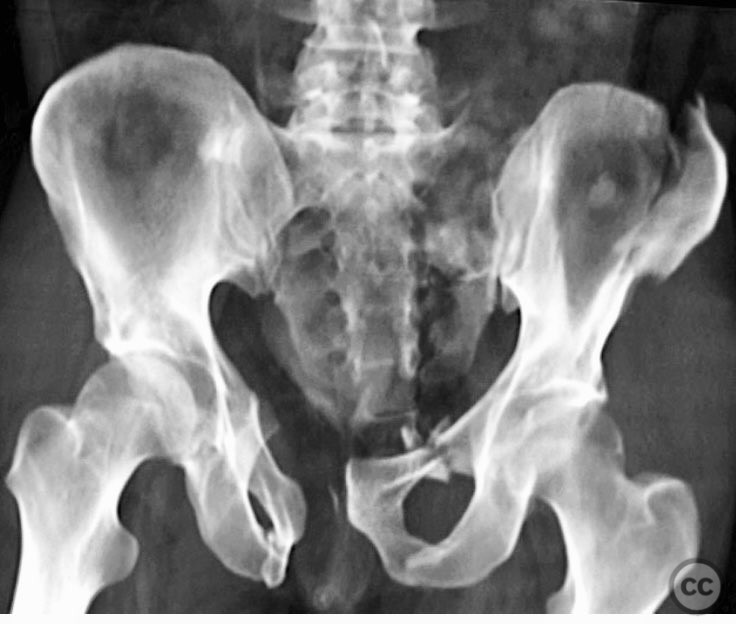

Pelvis - AO/OTA 6x